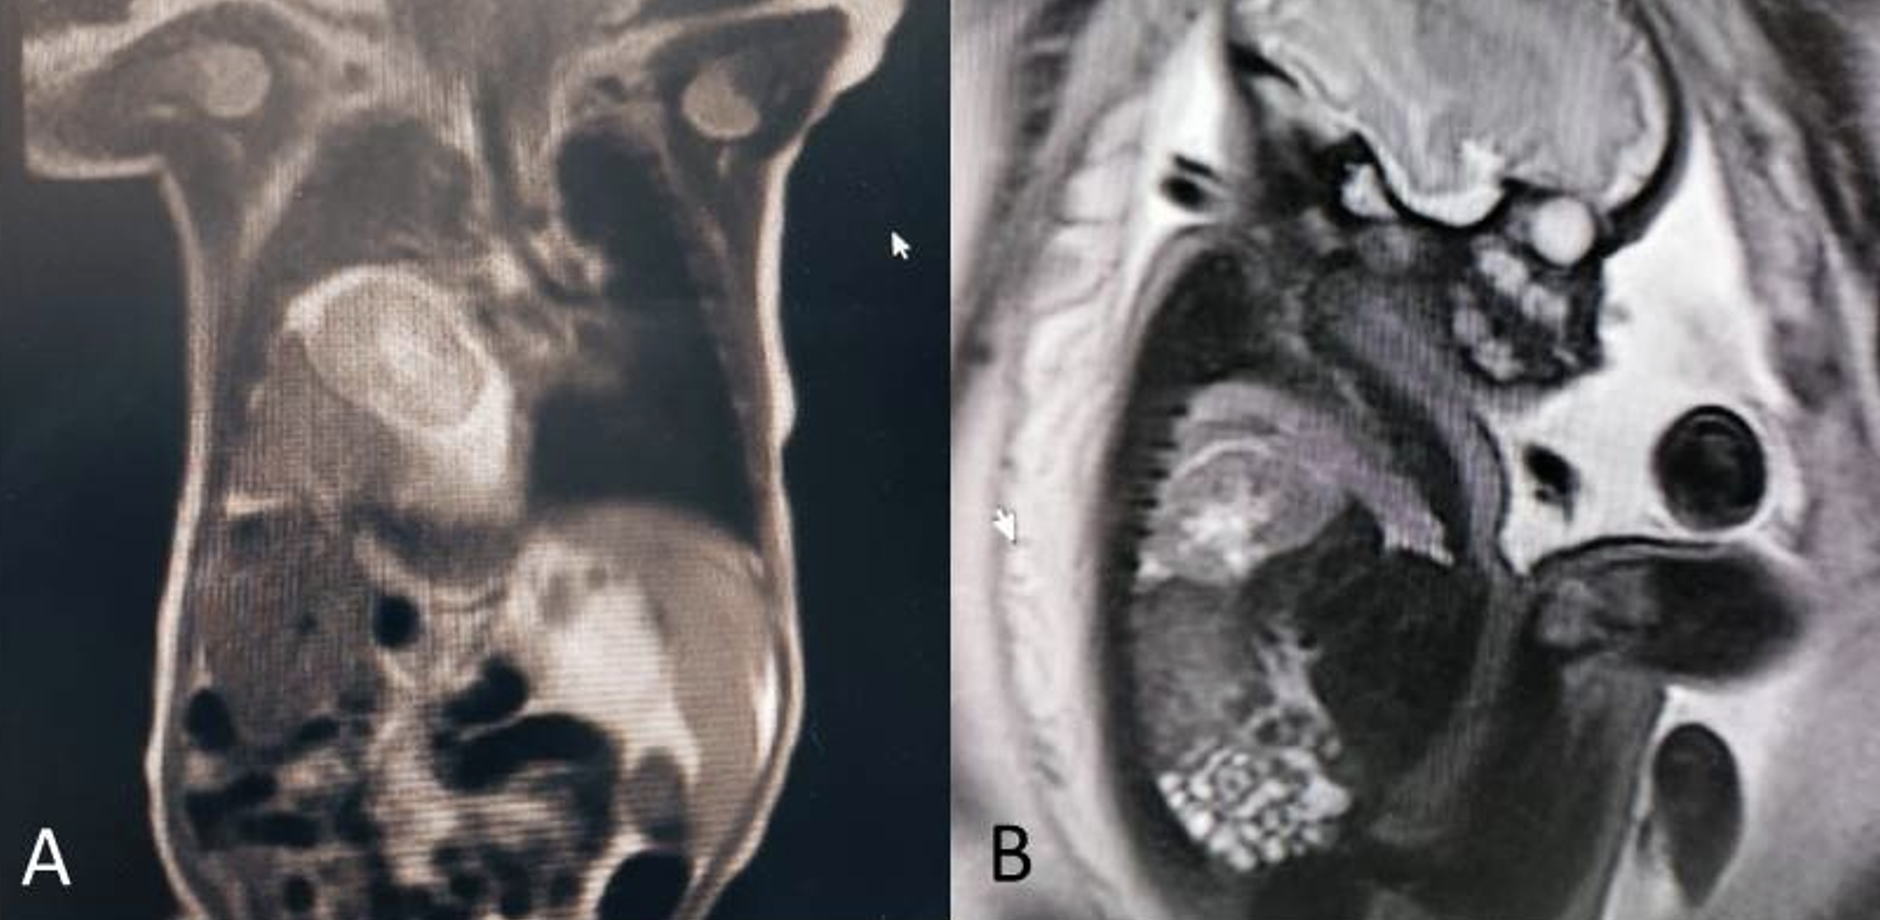

Se presenta el caso de un recién nacido masculino, producto de una unión no consanguínea, cuya madre tenía 24 años, dos gestaciones y un parto previo, sin antecedentes médicos relevantes. Había asistido a ocho controles prenatales en 2022 en los que no se detectaron marcadores de aneuploidías ni alteraciones en la anatomía fetal en las ecografías realizadas en las semanas 11-14 y 22. Sin embargo, en la ecografía de seguimiento realizada a las 28 semanas en una unidad de diagnóstico prenatal privada de la ciudad de Cali (Colombia), se observó en el corte subcostal de 4 cámaras cardiacas en el hemitórax derecho una imagen eco-mixta que comprimía el pulmón derecho contra la pared anterior del tórax y desplazaba el corazón hacia la izquierda, sin levocardia (Figura 1). Se identificaron dos ecogenicidades diferentes y se determinó que se trataba de un REI en el contexto de una hernia diafragmática. Por lo tanto, se ordenó una resonancia magnética fetal, que se realizó a las 31 semanas y mostró una hernia diafragmática derecha con herniación del hígado en los segmentos VII y VIII, y un riñón derecho intratorácico (Figura 2).